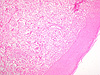

Paciente feminina de 19 anos, branca, em bom estado geral. Refere abaulamento com crescimento lento e progressivo há 1 ano, na região dos dentes 12 e13, assintomático. Rx- área radiolúcida, bem delimitada, atingindo 2cm no maior diâmetro

Paciente de 12 anos, masculino com lesão expansiva, de crescimento lento em maxila E.

Paciente 19 anos, com lesão de crescimento lento e progressivo, deformante da mandíbula. Realizada hemi-mandibulectomia. A radiografia mostrada é referente à peça cirúrgica.

Paciente feminina, 8 anos apresentando lesão expansiva na região maxilar D.